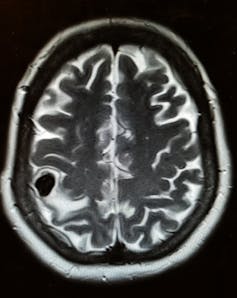

腦部掃描顯示,患者受豬肉寄生蟲感染。 Source: The Conversation